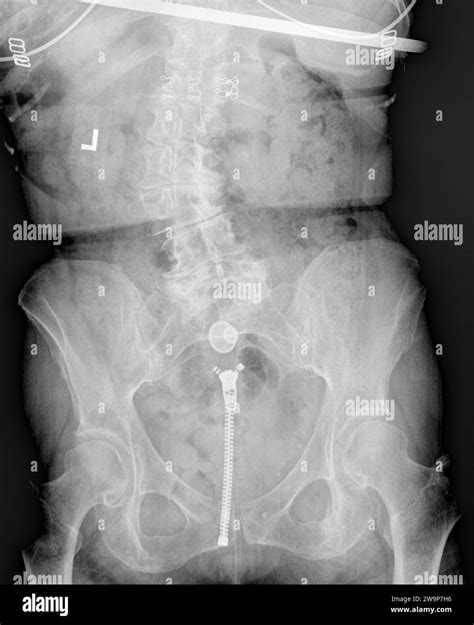

L'isterosalpingografia (HSG) è considerato l'esame di riferimento per la valutazione della pervietà tubarica. Questa procedura radiografica prevede l'iniezione di un mezzo di contrasto iodato attraverso la cervice e l'utero. Successivamente, vengono effettuate una serie di radiografie per osservare la distribuzione del liquido di contrasto all'interno delle tube. Se il liquido fluisce liberamente attraverso le tube, queste sono considerate pervie. Al contrario, un blocco o un restringimento indica un'ostruzione.